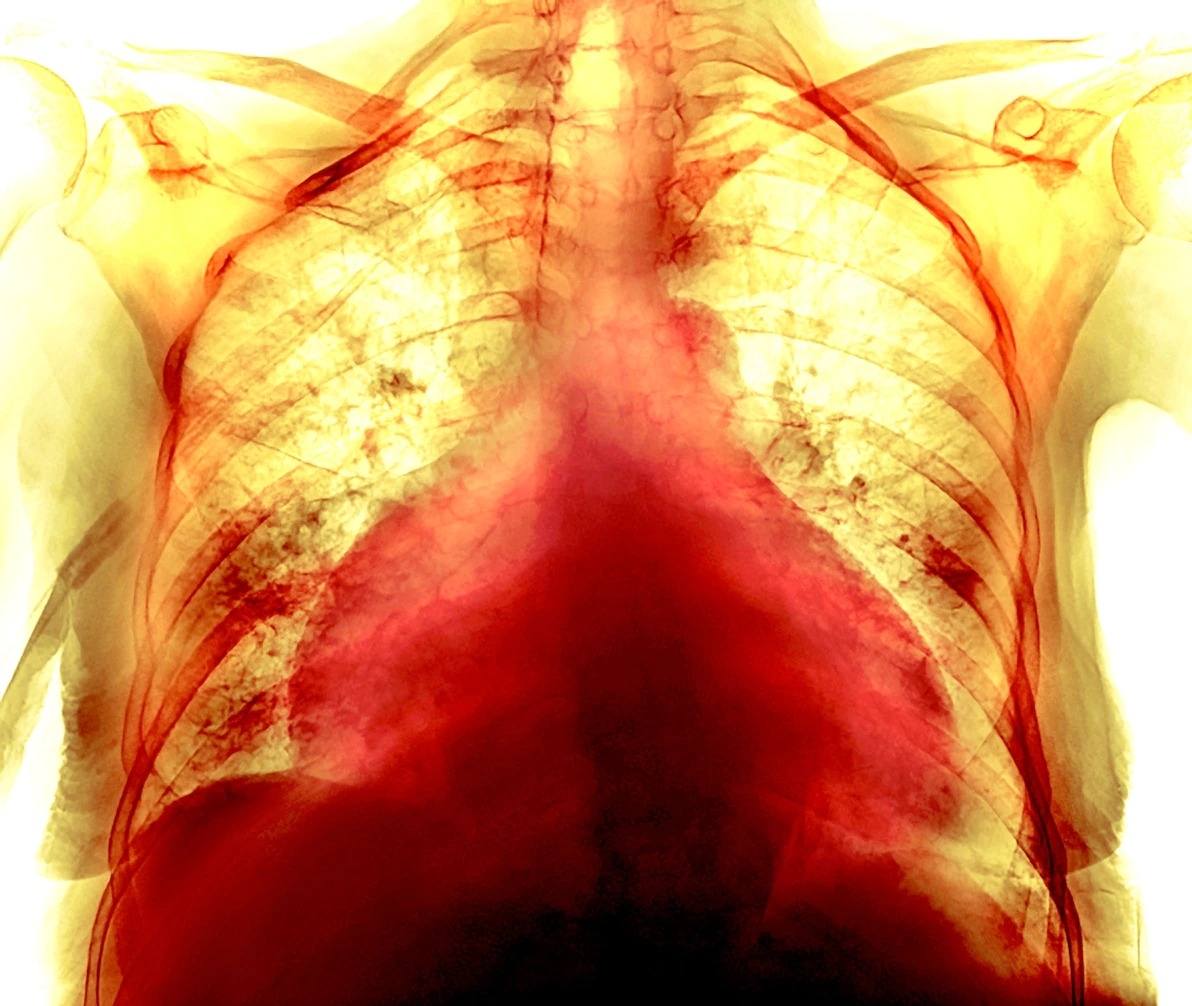

这张彩色胸腔X光影像显示一名74岁女性COVID-19病患的肥大心脏。有些病患从COVID-19康复的几个月后持续出现心血管症状──即使他们的胸腔扫描及其他检查结果都正常也一样。 PHOTOGRAPH BY P. MARAZZI/SCIENCE SOURCE